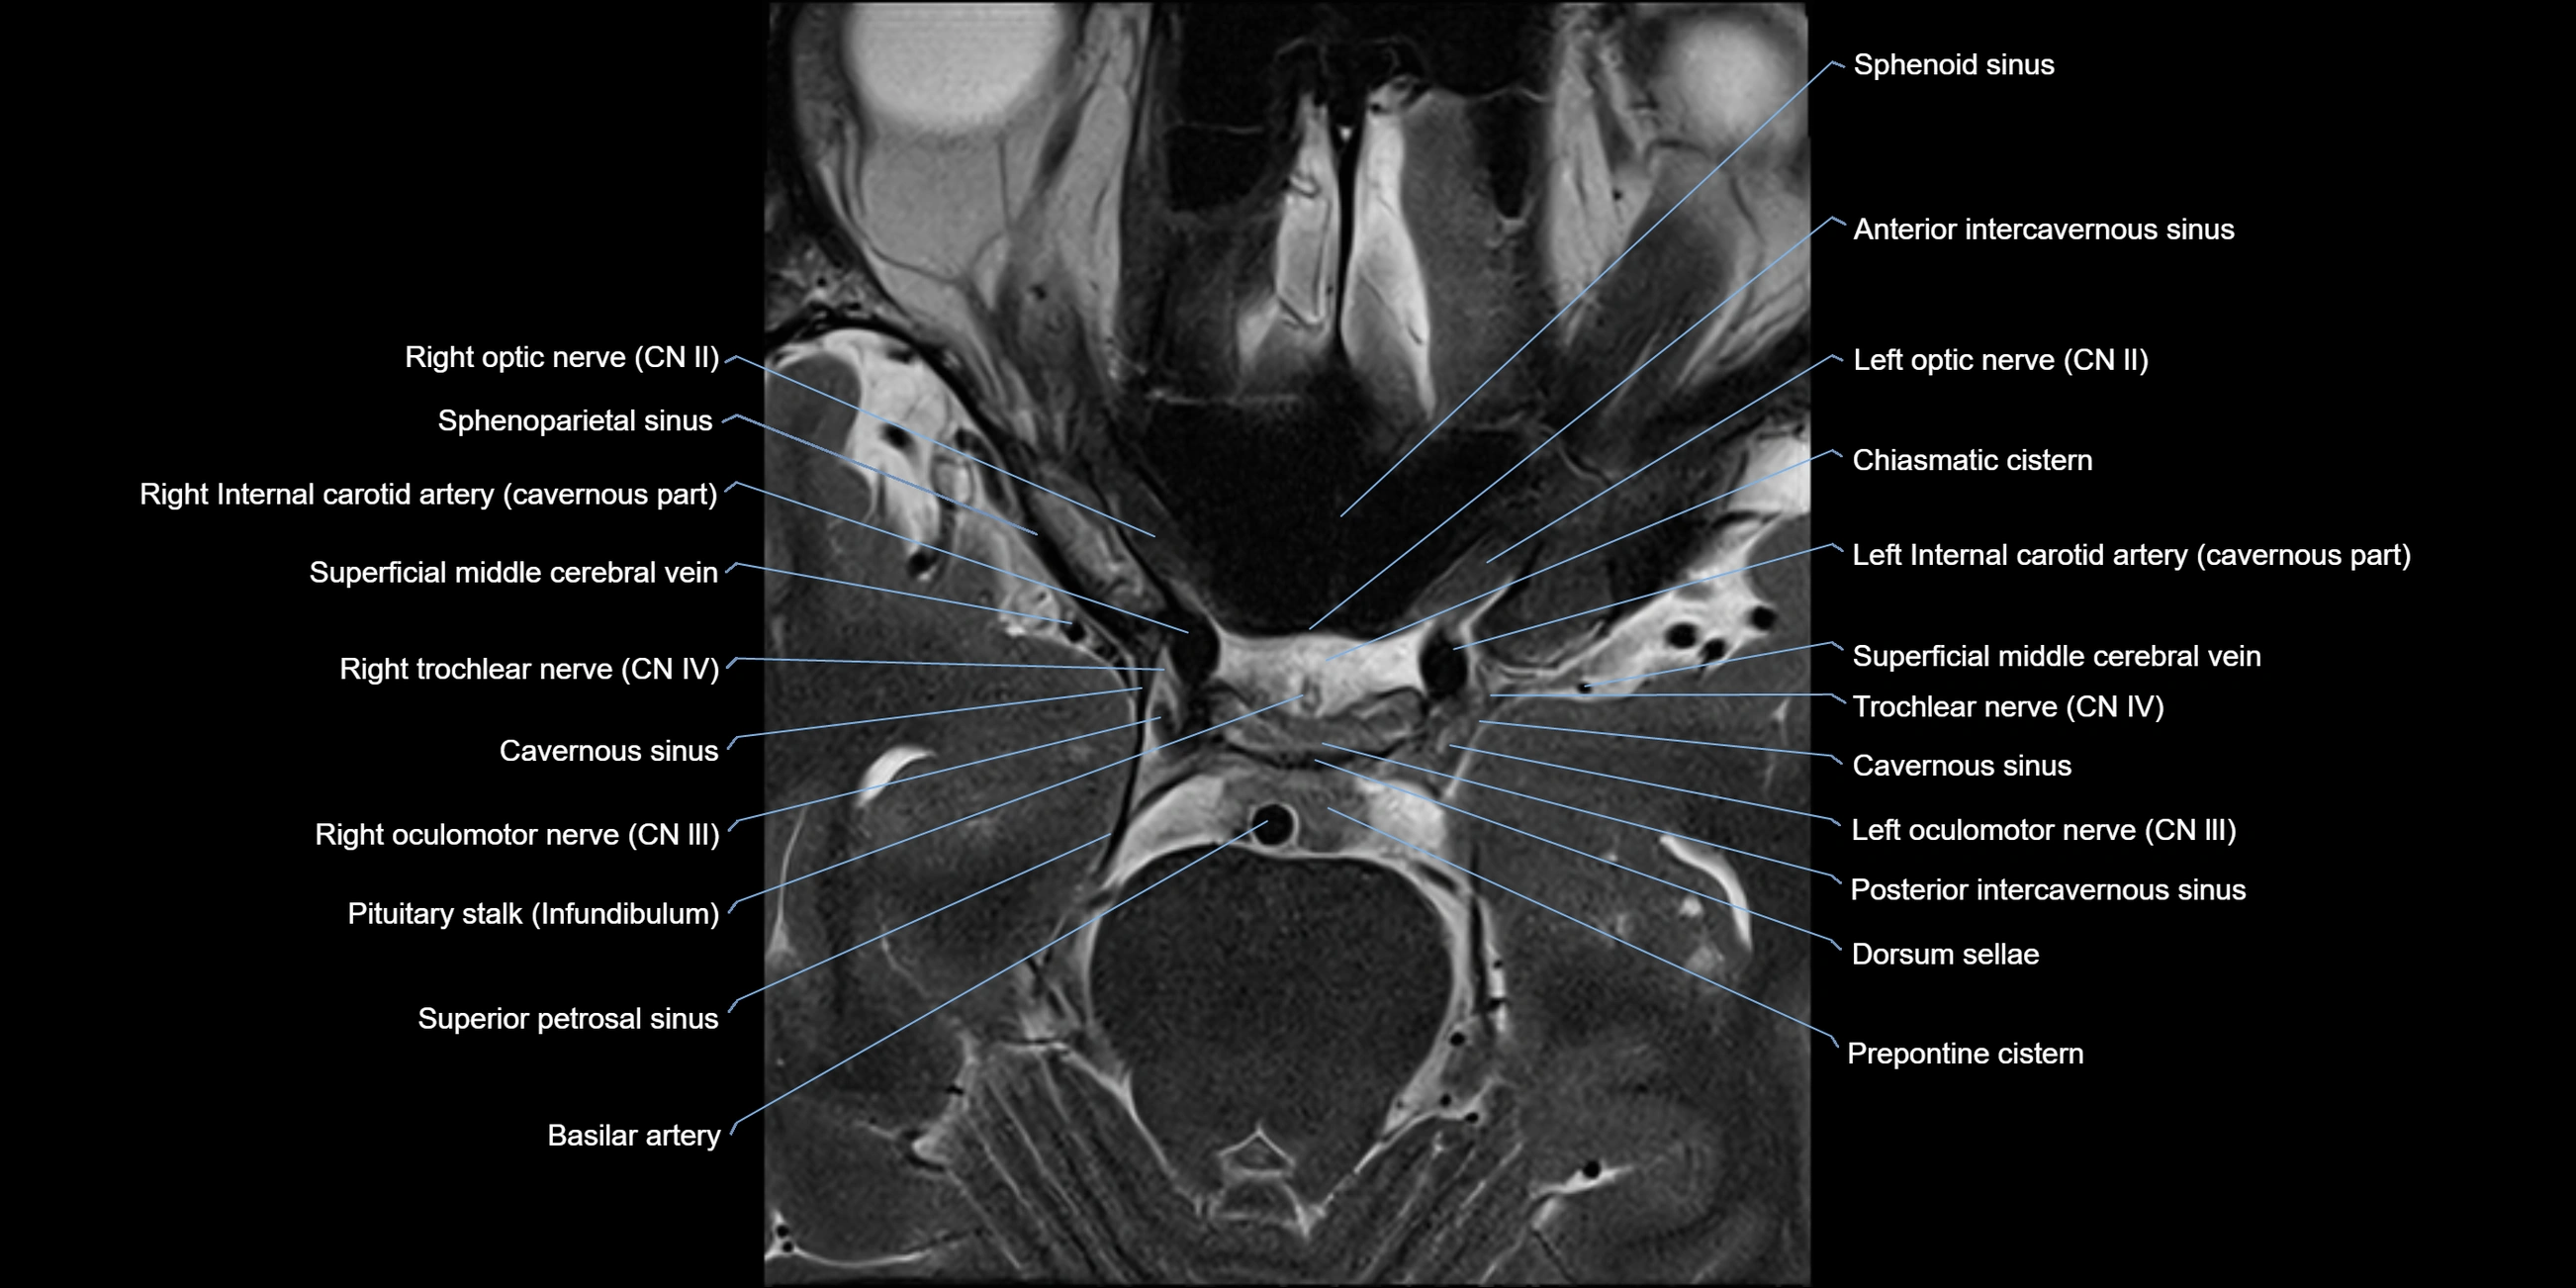

MRI Appearance

The abducens nerve is a small, thin, linear structure

Best visualized on high-resolution T2-weighted 3D MRI sequences (e.g., FIESTA or CISS)

Seen as a hypointense (dark) line running from the brainstem at the pontomedullary junction, traversing the prepontine cistern, and entering Dorello’s canal under the petrosphenoidal ligament, then into the cavernous sinus, and finally the orbit

May be challenging to visualize in standard MRI due to its small size

Pathology may be inferred by absence, displacement, or enhancement of the nerve

MRI images